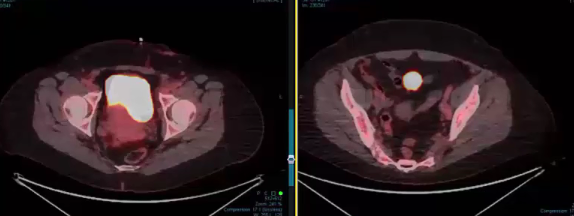

endometrial adenocarcinoma, para-aortic nodes, PET CT, diabetes, charcot arthropathy, groin nodes, pelvis, negative cervical margins, cisplatin, small bowel, Harkenrider, contouring, MRI, tumor, vaginal bleeding, relapse, persistence, cylinder, dose distribution, dosimetry, brachytherapy, fractio...

squamous cell carcinoma, dysplasia, PET, SIB, brachytherapy, endocervical, MRI, nodal location, inguinofemoral, right external iliac, CTV, deescalation, dosimetry, sigmoid, hysterectomy, concurrent chemoradiation, stenotic cervix, abdominal infection, external planning, avoid structure, antibioti...